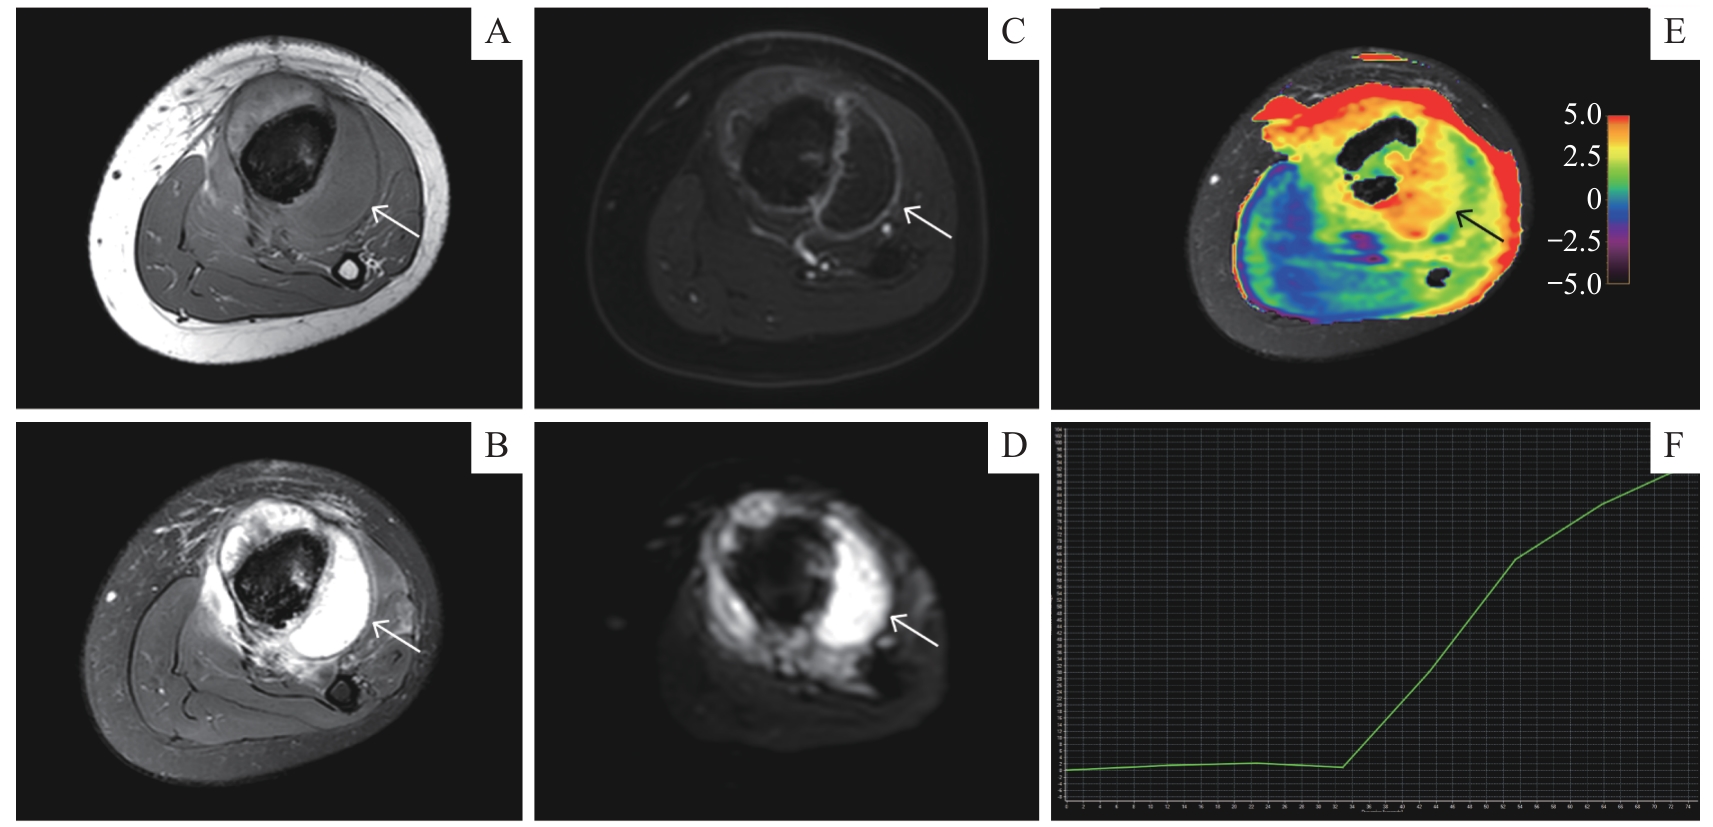

| APT | 4.52%±0.76% | 2.47% (0.56%) | 5.00 | <0.001 |

| ADC/(10 -3·mm 2·s -1) | 1.37±0.52 | 1.03 (0.66) | 44.00 | 0.527 |

| TIC(Ⅰ/Ⅱ/Ⅲ)/ n(%) | 3 (60.0)/1 (20.1)/1 (20.0) | 14 (48.3)/13 (44.8)/2 (6.9) | 1.59 | 0.453 |

| APT | 2.43%±0.23% | 3.67%±0.24% | 138.00 | <0.001 |

| ADC/(10 -3·mm 2·s -1) | 1.00 (0.66) | 1.31±0.65 | 75.00 | 0.643 |

| TIC(Ⅰ/Ⅱ/Ⅲ)/ n(%) | 13 (56.5)/9 (39.1)/1 (4.3) | 1 (16.7)/4 (66.7)/1 (16.7) | 3.42 | 0.181 |